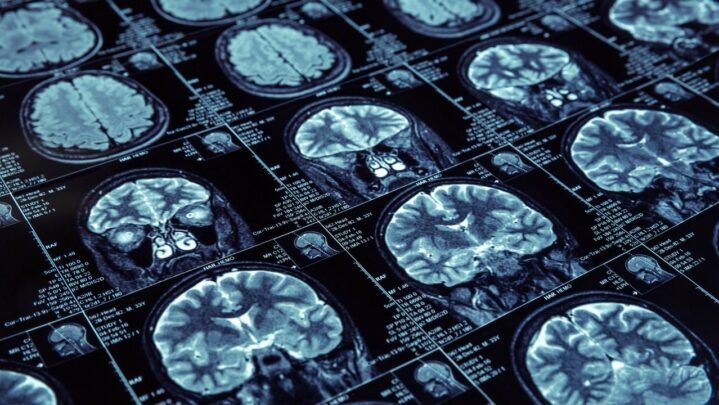

Because ADHD is a neurodevelopmental issue, high-tech brain scans based on blood flow and brain wave activity may be able to shed light on the problem.

Researchers employ a variety of brain scan technologies and methodologies to study the brains of ADHD patients. Single-photon emission computed tomography (SPECT), positron emission tomography (PET), and functional magnetic resonance imaging are just a few of them (fMRI).

SPECT brain scans demonstrate how the brain functions, whereas MRI and CT brain imaging investigations show how the brain is structured. SPECT basically indicates three things: good activity, excessive activity, and insufficient activity. It can also reveal indicators of brain trauma, toxic exposure, and drug and alcohol addiction, all of which can contribute to ADD/ADHD symptoms.